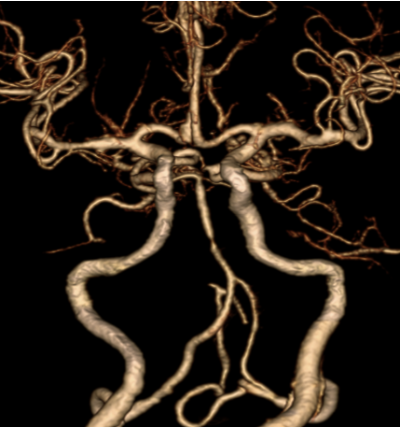

Ngay sau khi bơm thuốc tiêu sợi huyết ghi nhận sức cơ của bệnh nhân Đ. và N. đã cải thiện rõ rệt. Từ kết quả chụp CT mạch máu được thực hiện ngay sau bơm thuốc tiêu sợi huyết (Hình 2 và Hình 4) thấy cục huyết khối đã tiêu, tuy nhiên vẫn có sự hẹp của một động mạch lớn nội sọ ở cả 2 trường hợp.

| Hình ảnh hẹp động mạch thân nền của bệnh nhân P.T.N |